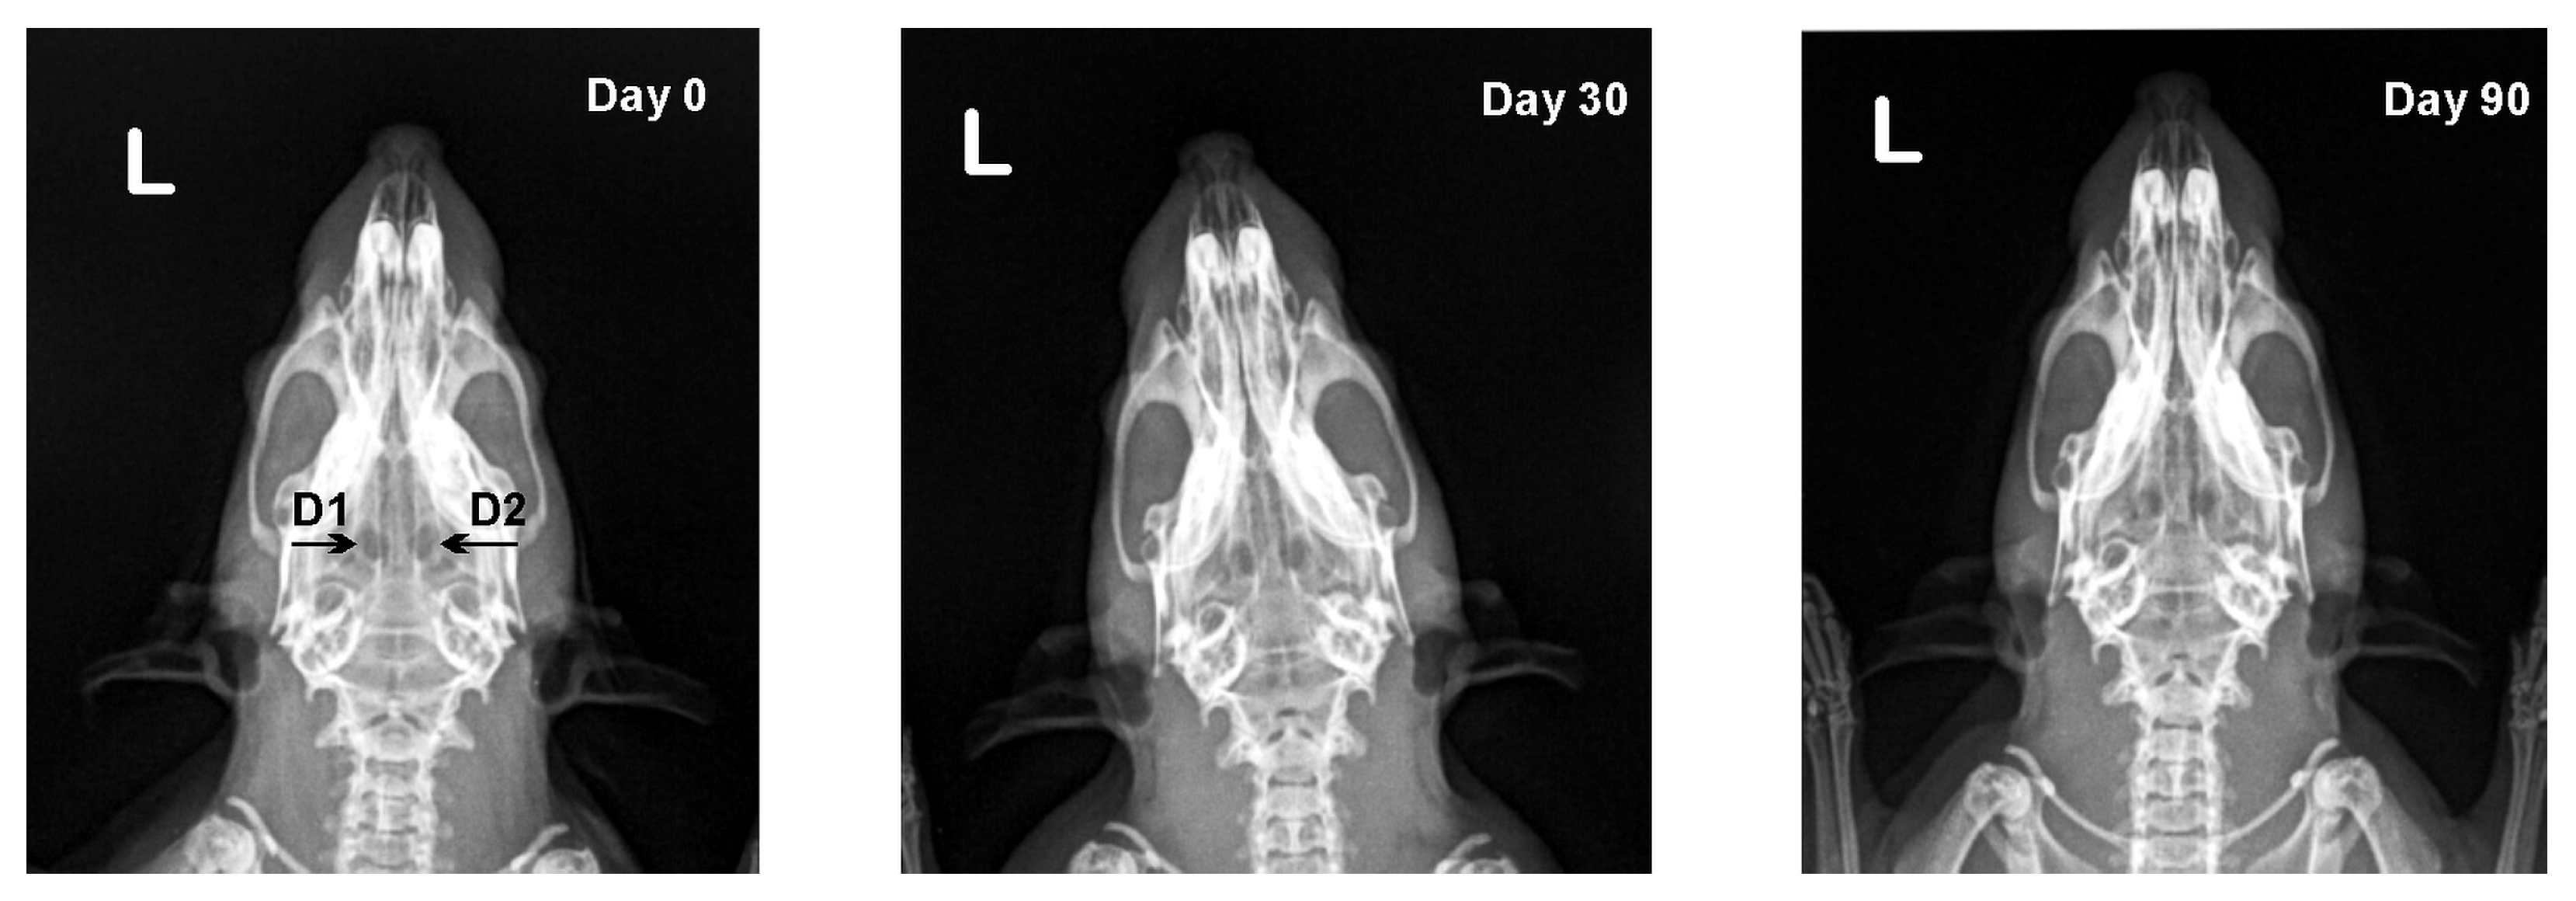

3.2. X-ray Results

| Defect | Day 0 | Day 30 | Day 90 |

|---|---|---|---|

| D1 | 0.92 ± 0.02 | 0.92 ± 0.03 | 0.93 ± 0.03 |

| D2 | 0.93 ± 0.02 | 0.93 ± 0.04 | 0.95 ± 0.04 |

| D3 | 0.92 ± 0.02 | 0.91 ± 0.03 | 0.90 ± 0.03 |

| D4 | 0.93 ± 0.01 | 0.92 ± 0.02 | 0.90 ± 0.02 * |